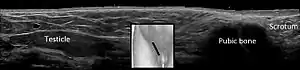

تشخیص

شایعترین معضل تشخیصی در افراد طبیعی، افتراق بیضه برگشتی (retractile testis) از نهانبیضگی است، که شایعتر از بیضههای واقعاً نزول نیافته هستند و نیازی به جراحی ندارند. در مردان عادی، با شل شدن یا انقباض عضله کرماستر، بیضه در کیسه بیضه به سمت پایین یا بالاتر حرکت میکند، این رفلکس کرماستریک در پسران شیرخوار بسیار فعالتر از مردان بزرگسال است. تشخیص بیضه قابل برگشت در کیسه بیضه از موقعیتی که در مجرای تحتانی اینگوینال وجود دارد دشوار است.